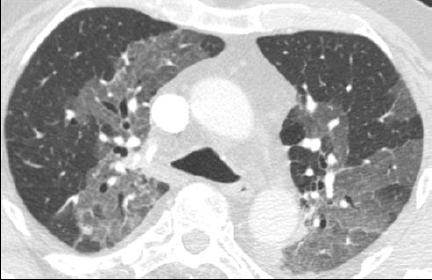

Micronodules

COCHE E. - 2021 - UCL

Cardio-thoracique DES SPECIALITE